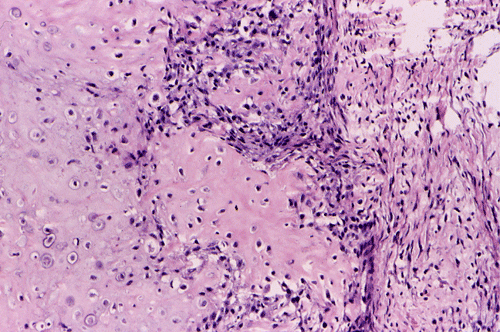

Pathology of the case:  An incisional biopsy yielded several small fragments of gritty, tan to translucent tissue. The histopathology varies in different parts of the tumor. In some areas, the lesion is composed predominantly of islands of neoplastic cartilage with focal osteoid formation and rimmed by spindle cells (Panel E). In other areas, densely packed spindle cells proliferation admixed with hypocellular fibrous tissues is present (Panel F). On high magnification, the spindle cells appear to be pleomorphic and hyperchromatic (Panel G). Mitotic figures are present but not numerous. No atypical mitoses are noted. Small foci of osteoid are best appreciated at higher magnification ("OS" in Panel G). It appears that this tumor has arisen from the medullary cavity and is best classified as a central osteosarcoma.

Osteosarcoma is a malignant tumor characterized by direct formation of bone or osteoid by the proliferating neoplastic cell. Other than sharing this characteristic, osteosarcoma is one of the most heterogeneous tumor from the histopathologic perspective.  The histologic features vary from different areas of the same tumor and among different tumors. In general, several major patterns are recognized: osteoblastic, chondroblastic, fibroblastic, giant-cell rich, small cell, telangiectatic,  and others. The amount of osteoid and ossified tissue can vary tremendously and it is not uncommon that it can only be found after careful search. The osteoid can form well-defined structures that mimic trabecular bone or as irregular deposits. The current trend is to classify osteosarcomas into low- and high-grade tumors. It is the histologic grade rather than tissue pattern that has greatest bearing on prognosis.

Similar to osteosarcomas arising from the flat bones and ribs (e.g., osteosarcomas of the pelvic bones), about 30% of the osteosarcomas of the jaws are chondroblastic type and contain a substantial amount of cartilage. Lobules of neoplastic cartilage may dominate the histologic picture in some cases and osteoid production by the neoplastic cells may occur only focally.  The cartilaginous differentiation can be heterogeneous and represent all stages of cartilaginous matrix formation. Stigmata of malignancies including nuclear pleomorphism, mitosis, atypical mitotic figures, and necrosis can all be seen in osteosarcomas.